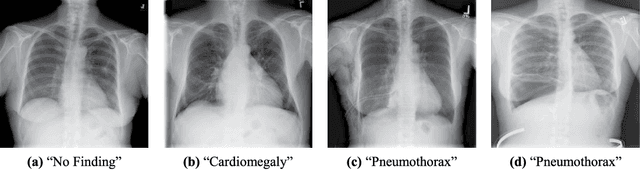

Abstract:Growing radiologic workload and shortage of medical experts worldwide often lead to delayed or even unreported examinations, which poses a risk for patient's safety in case of unrecognized findings in chest radiographs (CXR). The aim was to evaluate, whether deep learning algorithms for an intelligent worklist prioritization might optimize the radiology workflow and can reduce report turnaround times (RTAT) for critical findings, instead of reporting according to the First-In-First-Out-Principle (FIFO). Furthermore, we investigated the problem of false negative prediction in the context of worklist prioritization. To assess the potential benefit of an intelligent worklist prioritization, three different workflow simulations based on our analysis were run and RTAT were compared: FIFO (non-prioritized), Prio1 (prioritized) and Prio2 (prioritized, with RTATmax.). Examination triage was performed by "ChestXCheck", a convolutional neural network, classifying eight different pathological findings ranked in descending order of urgency: pneumothorax, pleural effusion, infiltrate, congestion, atelectasis, cardiomegaly, mass and foreign object. The average RTAT for all critical findings was significantly reduced by both Prio simulations compared to the FIFO simulation (e.g. pneumothorax: 32.1 min vs. 69.7 min; p < 0.0001), while the average RTAT for normal examinations increased at the same time (69.5 min vs. 90.0 min; p < 0.0001). Both effects were slightly lower at Prio2 than at Prio1, whereas the maximum RTAT at Prio1 was substantially higher for all classes, due to individual examinations rated false negative.Our Prio2 simulation demonstrated that intelligent worklist prioritization by deep learning algorithms reduces average RTAT for critical findings in chest X-ray while maintaining a similar maximum RTAT as FIFO.